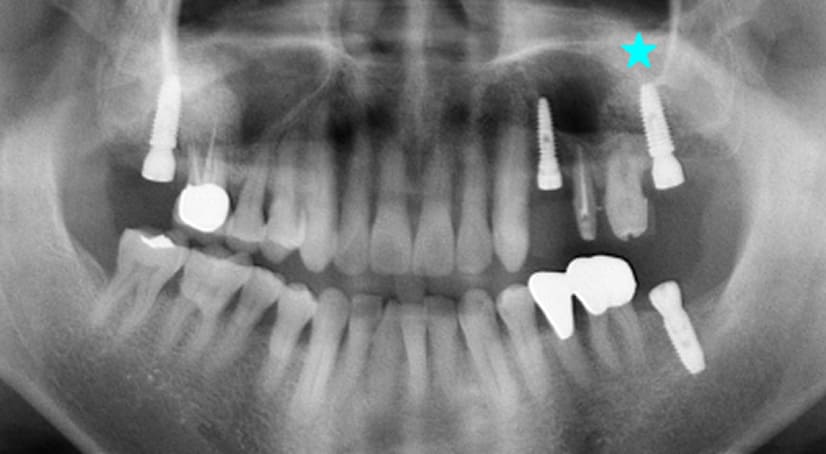

13+ 年

-

种植体植入 2012年10月 -

最终修复体 2013年1月 -

随访:13年 2025年3月